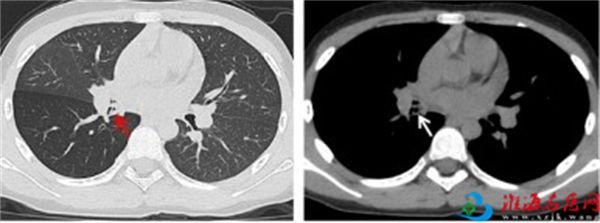

当日下午,徐医附院耳鼻喉科对口帮扶专家曹恒明主任医师在商洛市商州区人民医院门诊接诊一名“含咬笔帽时突发呛咳”的8岁小学生,考虑支气管异物可能,已紧急进行胸部三维CT检查,并联系呼吸与危重症医学科孙理想副主任医师。孙理想立即前往门诊查看患儿,发现患儿已有阵发性咳嗽症状,听诊右下肺呼吸音完全消失。胸部CT显示右中间段支气管异物合并阻塞性炎症,右肺下叶空气潴留征象。经过仔细查看胸部CT,孙理想判断笔帽异物可能开口朝下,这大大增加了取出的难度。目前,经支气管镜异物取出术是首选的解决方法。由于商州区人民医院之前未开展过全麻支气管镜手术,曹恒明与孙理想立即联系了麻醉科和手术室等多科室医生进行了综合讨论,完善术前准备后决定在急诊进行全麻下的经支气管镜异物取出术。